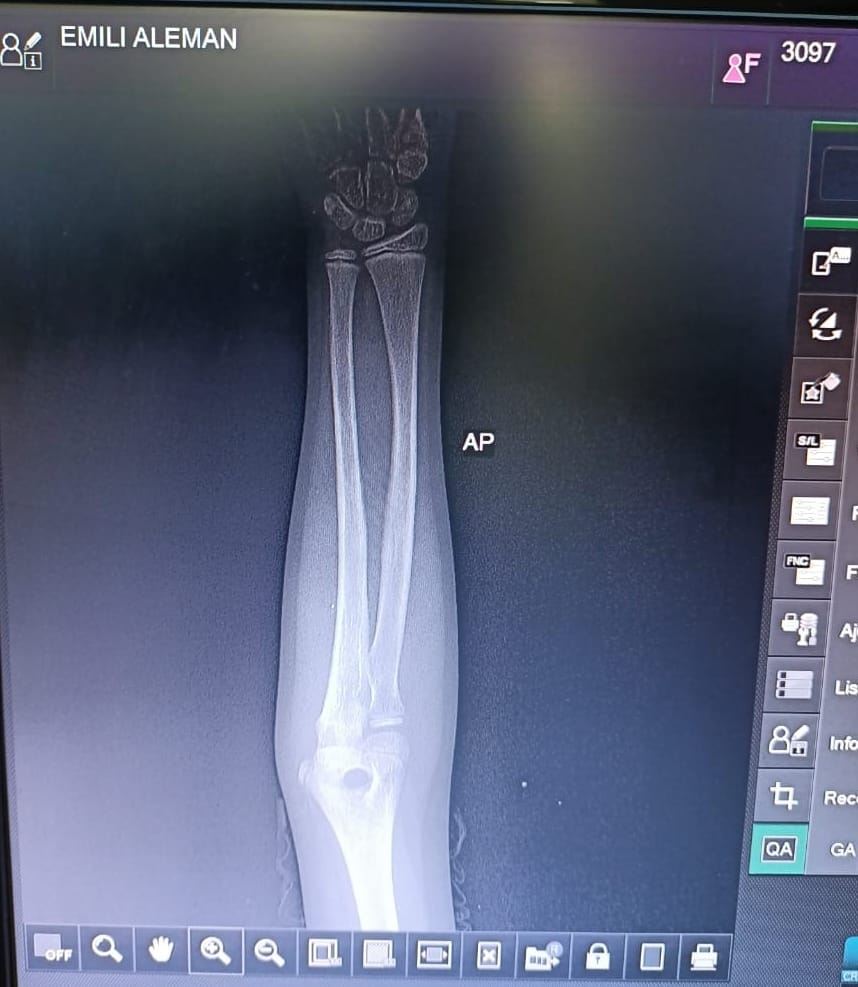

Como en anteriores casos, el personal de la Secretaría de la Defensa Nacional acudió a los hospitales para asegurar que iba a hacerse cargo de los gastos médicos, pero no lo hicieron. Una de las personas heridas, es una niña de 9 años, que recibió dos esquirlas de bala en el antebrazo derecho.